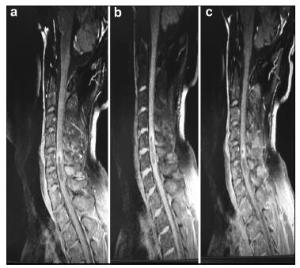

20170512093647  Figure 2 a–c. Postoperative MR images of Case 1.